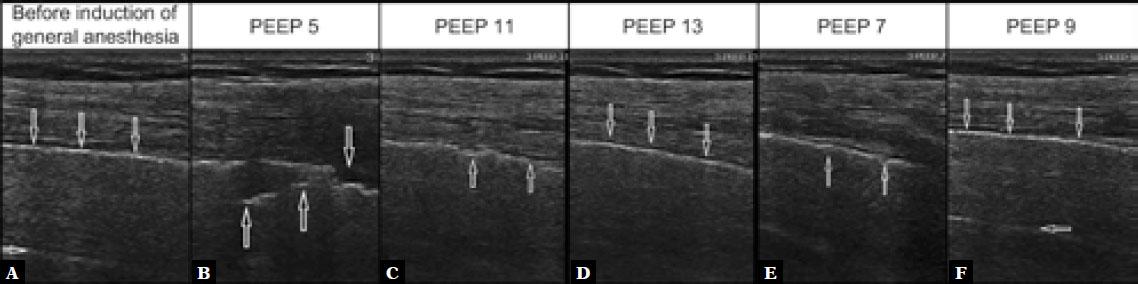

Fig. 1